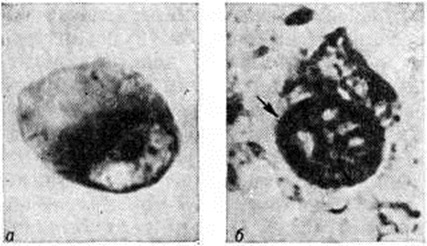

Патологическая анатомия. Патологоанатомические изменения при Пика болезнь характеризуются избирательной атрофией главным образом коры и белого вещества полушарий головного мозга. Иногда атрофия в значительно меньшей степени захватывает подкорковые узлы и стволовые отделы. Различают атрофию преимущественно лобных (рисунок 1) или височных долей, нередко — комбинированное их поражение. Часто в процесс вовлекаются теменные доли, однако изолированное их поражение, так же как и атрофия затылочных долей, встречается крайне редко. При атрофии лобных долей прецентральные извилины обычно остаются сохранными. Атрофия развивается, как правило, в симметричных участках обоих полушарий, иногда с большей выраженностью в левом и крайне редко — в правом полушарии.

Рис. 1. | ||